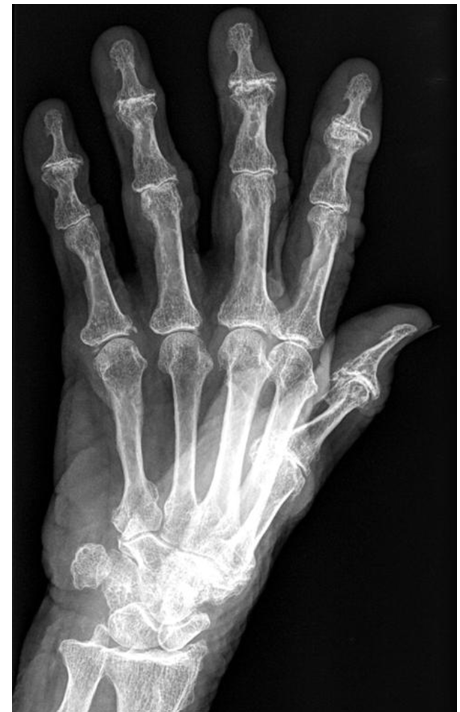

EROSÕES EM SACA BOCADO EM ARTICULAÇÕES PERIFÉRICAS

PENSAR EM